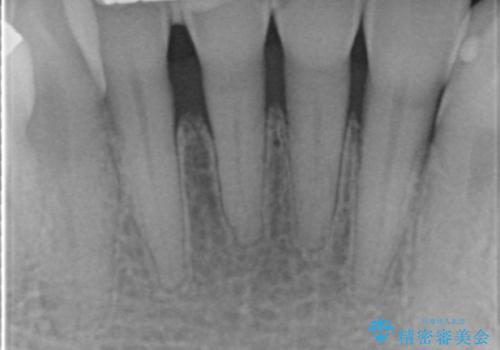

前歯がかけた、ぐらぐらする 60代女性

- 下の前歯が欠けてぐらぐらすることを主訴に来院された患者様です。

以前行った奥歯の治療により下顎前歯の動揺は改善傾向にあり顕著ではなかったのですが、欠けて黒くなっていることと少しの動揺が気になるとのことでした。

元気なうちに治療しておきたいという患者様の強いご希望により、下顎前歯の連結補綴と欠けている小臼歯の補綴治療を行いました。